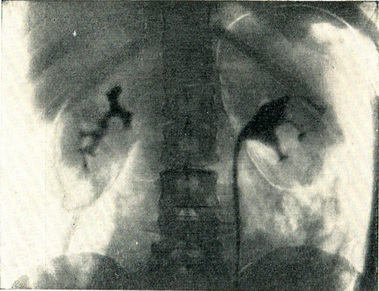

На оглядовій рентгенограмі часто виходять тіні нирок, що дозволяє встановити збільшені і неправильні контури нирки, ураженої пухлиною. Вирішальне значення має ретроградна пієлографія. Якщо пухлина проростає або здавлює ниркові келихи, на ретроградної пиелограмме видно відповідні зміни їх (рис. 101 і 102). Якщо пухлина проросла в ниркову балію, виявляється дефект наповнення. Контрастна речовина може зовсім не проникнути в балію, якщо пухлина проросла заповнює її порожнину. Пухлини, що походять з нижнього полюса, часто відтісняють верхній відрізок сечоводу в сторону хребта у вигляді дуги, зверненої опуклістю в медіальну сторону (див. рис. 102). Важливим симптомом є асиметричне розташування ниркової миски по відношенню до нирці. При пухлини, витікаючої з полюса нирки, балія зміщується до протилежного полюса (рис. 103).

Рис. 102. Пухлина нижнього полюса лівої нирки, оттесняющая лівий сечовід у бік хребта. Нижня чашка ампутована, середня відсунута догори. Ретроградна пиелоуретерограмма.